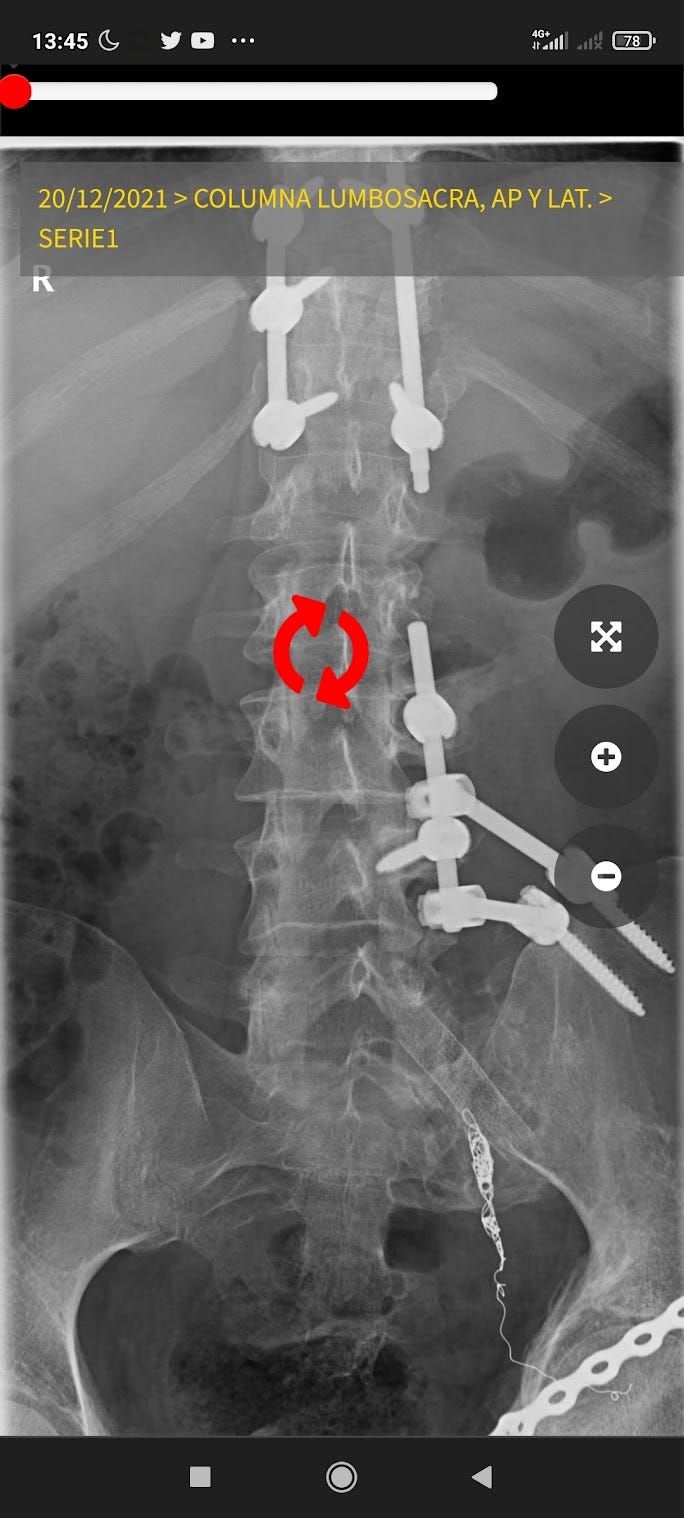

Me dijeron que no volvería a caminar, en cambio camino, corro, y monto en bici. A veces, que te digan eso, que no vas a volver a hacer tal cosa, puede ser peor losa, que el propio dolor que te causa esa pierna que no se mueve.